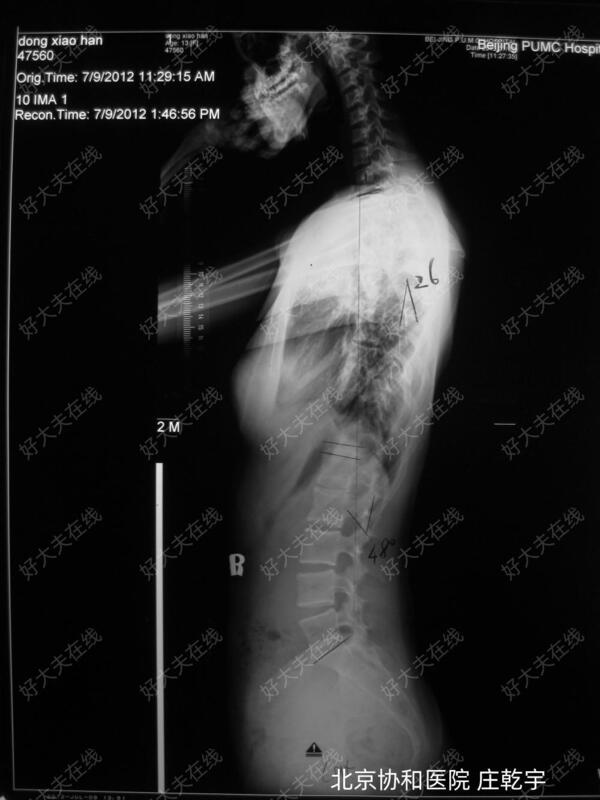

患者13岁女性,脊柱侧弯呈现三弯形态,包括上胸弯(34度)、主胸弯(52度)和腰弯(28度)。所以术前制定方案最主要的问题是这三个弯究竟哪个需要融合?哪个不需要融合?不融合的弯会不会自动恢复,术后会不会再加重?从术前影像学看,主胸弯度数最大,52度,需要融合;上胸弯32度,Bending相上30度,提示其比较僵硬,同样需要融合;腰弯28度,顶椎旋转小于2度,无明显胸腰椎后凸,Bending相柔韧性超过70%。考虑可以不融合,推测术后腰弯可自动减小。术前方案为矫正上胸弯及主胸弯,保留腰弯活动度,固定节段为T2-T12。